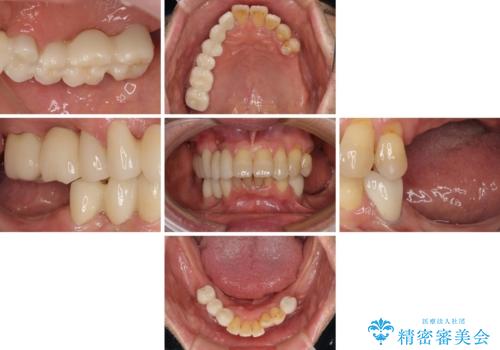

より適合の良い義歯とするため、セラミッククラウンなどは義歯の設計に合わせた土台の歯となるよう全て再製作をし、安定感に優れた義歯を製作することができました。

装着感の良い入れ歯を作りたい 金属床を使用した適合の良い部分床義歯